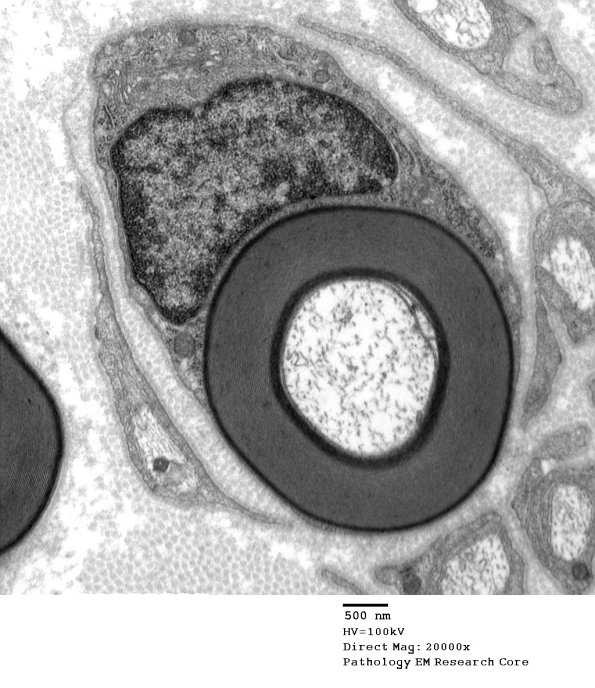

6A1-4 This unusual axon shows two-tone myelin which is not accompanied by an abnormality in myelin periodicity, thought to reflect osmium penetration problems. (electron micrographs)